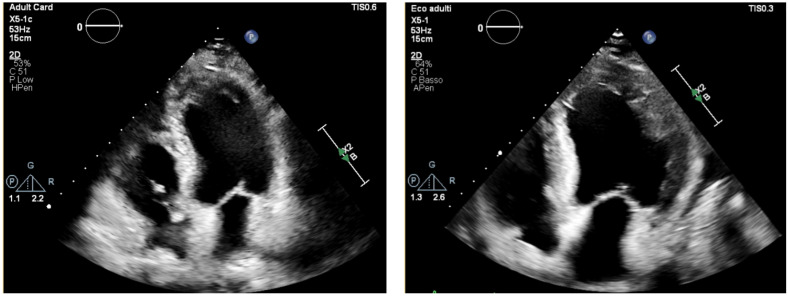

嗜酸性心肌炎(EM)是一种罕见且具有潜在致命性的急性心肌炎。目前,没有有效的诊断标准存在,明确的诊断依赖于心肌内膜活检(EMB)并非没有围手术期并发症。本综述旨在探讨多模态成像方法如何支持早期诊断,减少对EMB的依赖,实现风险分层和监测对抗炎治疗的反应。特别是,超声心动图在疑似EM中提供了快速和有用的信息,而心脏磁共振(CMR)由于能够提供准确的组织特征,仍然是诊断的非侵入性金标准。此外,正电子发射断层扫描/计算机断层扫描(PET/CT)和心脏CT (CCT)可能提供有价值的见解,特别是当超声心动图图像质量差或CMR禁忌或不可用时。根据我们的经验和目前的文献,最佳的多模态成像方法应该只对高风险或不确定的病例保留EMB。此外,该策略提供了补充信息,支持临床决策和优化长期结果。

Eosinophilic myocarditis (EM) is a rare and potentially fatal form of acute myocarditis. Currently, no validated diagnostic criteria exist, and definitive diagnosis relies on endomyocardial biopsy (EMB) not devoid of periprocedural complications. This review aims to explore how a multimodality imaging approach can support early diagnosis, reduce reliance on EMB, enable risk stratification and monitor the response to anti-inflammatory therapy. In particular, while echocardiography provides rapid and useful information in suspected EM, cardiac magnetic resonance (CMR) remains the non-invasive gold standard for diagnosis due to its ability to provide accurate tissue characterization. Moreover, positron emission tomography/computed tomography (PET/CT) and cardiac CT (CCT) may offer valuable insights, particularly when echocardiographic image quality is poor or CMR is contraindicated or unavailable. Based on our experience and current literature, an optimal multimodality imaging approach should reserve EMB only for high-risk or inconclusive cases. Furthermore, this strategy offers complementary information, supporting clinical decisions and optimizing long-term outcomes.